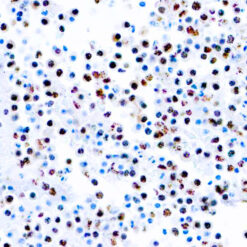

NUT1

NUTM1 is a Protein coding gene. Diseases associated with NUTM1 include NUT Midline Carcinoma and Spindle cell Carcinoma. The molecular weight of this antigen is 120kDa. Among its related pathways are Chromatin regulation/ Acetylation. An important paralog of this gene is NUTM2G. Plays a role in the regulation of proliferation. Regulates TERT expression by modulating SP1 binding to TERT promoter binding sites.

| Cellular Localization | Cytoplasmic, Nuclear |

| Positive Control Tissue | Testis |